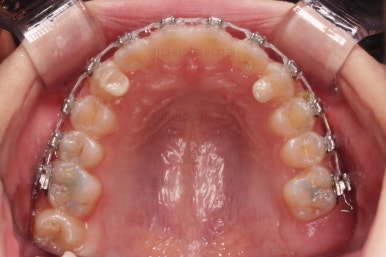

앞니의 각도가 앞으로 살아난 것이 보이실 거에요.

자연스럽게 과개교합 경향도 개선되어 어금니로 물었을 때 아래 앞니가 점점 보이기 시작하네요.

과개교합, 옥니, 앵글씨 2급 부정교합 모두 좋아지고 있어요.

앞니 각도가 매우 좋아졌고요.(옥니 개선) 위아래 앞니가 덮는 정도도 개선이 되었어요.(과개교합, 딥바이트)

엉성했던 어금니 맞물림도 매우 좋아졌어요.(앵글씨 2급 부정교합 개선)